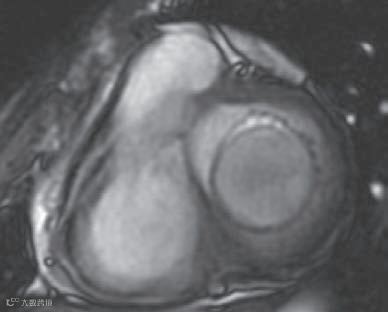

显示肿物边界清晰,有包膜,内部结构均匀,但未发现实性病变(图10和11)。以上检查均未显示肿瘤侵犯的证据,如房间隔不均匀或增厚,以及肿瘤向其他心腔延伸。

图10

图11